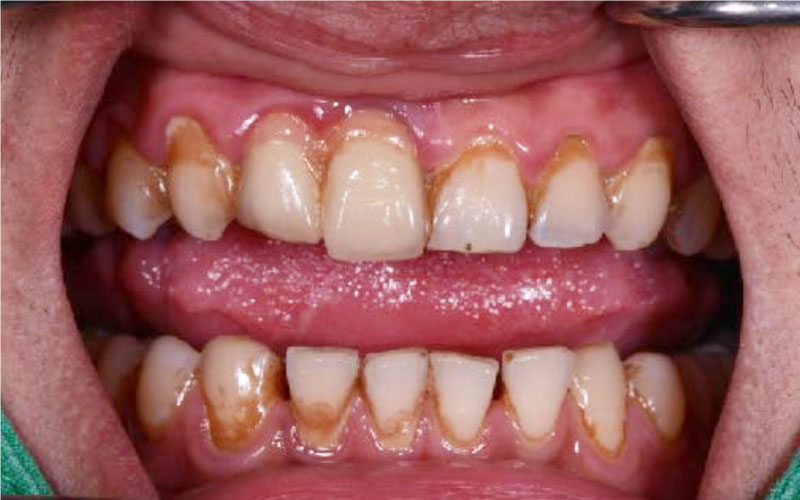

Before

• 牙齒染色

• 茶垢、菸垢附著

After

• 全口噴砂